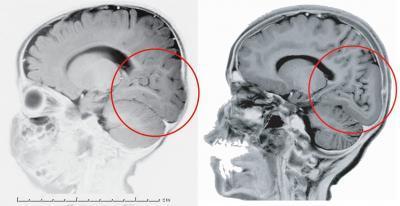

Fijémonos en la siguiente imagen:

En la izquierda tenemos un cerebro normal y en la derecha un cerebro de alguien que tiene una mutación en el gen LAMC3. Al observar las zonas del circulo podemos ver que la persona con la mutación no tiene las circunvalaciones exteriores del cortex, en su caso la zona está lisa. El gen LAMC3, parece estar implicado en el desarrollo de esas típicas circunvalaciones del cortex de nuestros cerebros, al menos en lo que al cortex occipital se refiere. Un pequeño cambio en dicho gen y las circunvalaciones no se manifiestan.